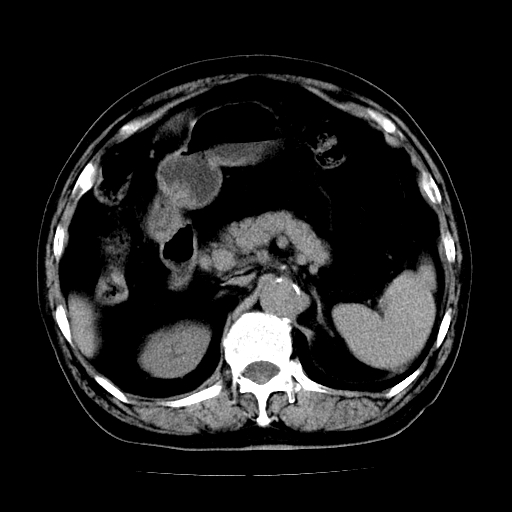

男,71岁,皮肤黄染四天。

肝内外胆管及胆总管上段扩张,考虑为梗阻所致,建议mrcp检查。

考虑胆总管癌并肝内外胆管扩张。

胆管癌并肝内外胆管扩张。

支持考虑胆总管癌并肝内外胆管扩张。 局部应薄扫。心包钙化。

胰腺上端胆总管内见软组织影,强化不明显,结合临床,还是考虑低位梗阻性黄疸,胆总管癌可能性大